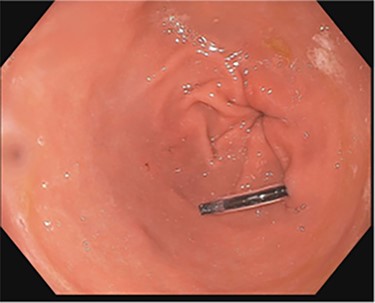

A 43-year-old incarcerated woman with borderline personality disorder and a long history of swallowing various foreign objects in periods of stress presented to the emergency department after swallowing a cup of bleach. Her surgical history was significant for multiple celiotomies for retrievals of purposefully ingested foreign bodies. During evaluation, she also admitted to swallowing an ink pen 3 weeks prior to swallowing the bleach for which she did not seek medical evaluation. She reported no food intolerance or changes in bowel function secondary to swallowing these objects. She presented with mild abdominal pain and cramping, and her vital signs and laboratory investigations were all within normal limits. Her abdominal exam was notable for mild tenderness to palpation diffusely. Computed tomography (CT) of the abdomen (Fig. 4) showed a linear foreign body in the distal gastric antrum penetrating the inferior wall and extending into the adjacent peritoneal fat. No free air or free fluid was appreciated. Initial esophagogastroduodenoscopy (EGD) was significant for mild erythema and edema to the esophageal and duodenal mucosa as a result of the caustic ingestion, and the pen was found to be deeply perforating the stomach antral wall with no associated ulcer or edema (Fig. 1). The depth at which the foreign body was lodged was uncertain, so there was concern for organ involvement outside of the gastric wall. Repeat EGD was done to assess for manifestations of esophageal, gastric or duodenal injuries from her caustic ingestion, and it revealed normal gastric mucosa (Fig. 2). A joint case was planned with the gastroenterology service for endoscopic foreign body retrieval, possible laparoscopic retrieval and gastric repair and possible open retrieval and gastric repair. The patient was taken to the operating room for the third EGD, which revealed spontaneous migration of the foreign body from the perforation site into the lumen of the gastric body (Fig. 3a). Additionally, there was spontaneous closure of the site of previous perforation (Fig. 3b and c). The ink pen was easily removed transorally using an endoscopic snare, and no further surgical intervention was required. After the procedure, the patient reported complete resolution of her abdominal pain and was able to tolerate a regular diet without problems.

Subsequent EGD 3 days later; gastric antrum with foreign body perforating through the gastric wall; normal gastric mucosa after ingestion of bleach.